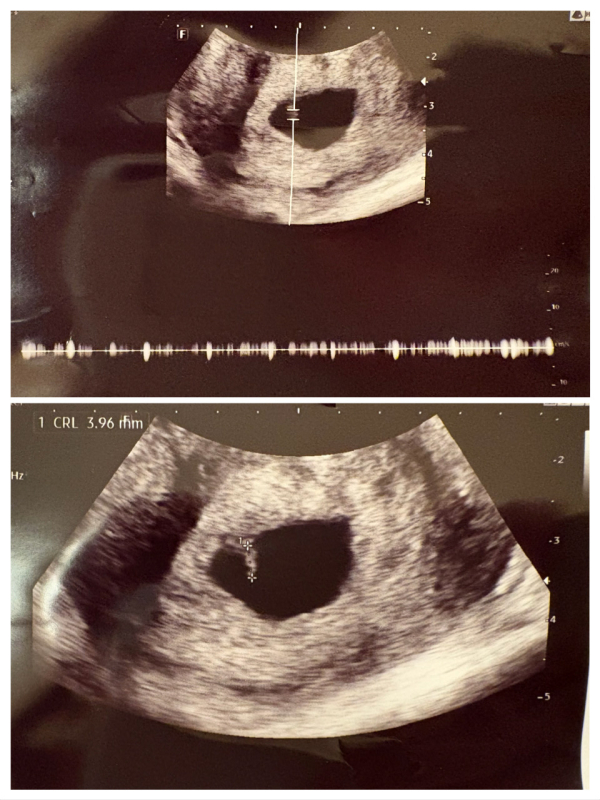

推定排卵日を2w0dとした場合、7w3dにあたる9/17に初診で受診しましたが、胎芽は約4ミリ、心拍数は140でした。ドクターによると胎芽の大きさは6w3d相当とのことで、「排卵が遅れたのかもしれない」と言われました。

(余談ですが、内診では胎嚢の大きさは測定されませんでしたが、後で自分でエコー写真を測ったところ、23〜24ミリ程度でやっぱりこれも6週半ば相当でした。参考までにエコー写真添付します)